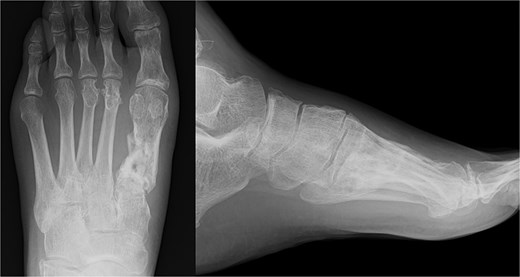

The external fixator was removed 4 weeks after the first surgery. Full weight-bearing was allowed 6 weeks after the operation. The plate was removed after confirming bone union. The patient was able to return to agricultural work 6 months postoperatively, and the American Orthopedic Foot and Ankle Society score 1 year post-surgery was 84. The follow-up radiography image taken at this stage is shown in Fig. 4.